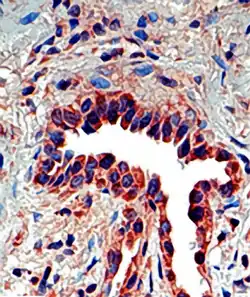

Osteopontin seen in a lung tissue sample from a patient with idiopathic pulmonary fibrosis.

Osteopontin is expressed in a variety of tissue types including cardiac fibroblasts,[25] preosteoblasts, osteoblasts, osteocytes, odontoblasts, some bone marrow cells, hypertrophic chondrocytes, dendritic cells, macrophages,[26] smooth muscle,[27] skeletal muscle myoblasts,[28] endothelial cells, and extraosseous (non-bone) cells in the inner ear, brain, kidney, deciduum, and placenta. Synthesis of osteopontin is stimulated by calcitriol (1,25-dihydroxy-vitamin D3).